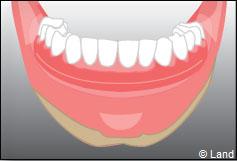

Situation clinique terminée